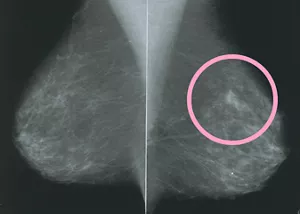

● マンモグラフィ

乳房はやわらかい組織でできているためマンモグラフィという専用のX線撮影装置で撮影します。

マンモグラフィは乳がんをはじめとする乳房にできる病気をほとんど見つけることができ、しこりとして触れないごく早期の乳がん(石灰化)も発見できます。

撮影自体は5分程度。X線を使いますがその量はごくわずかでほとんど危険はありません。